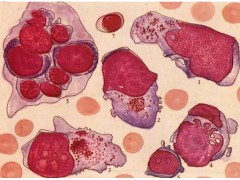

皮肤黑色素瘤细胞,SK-HEL-1

【规    格】1株/1ML

【储存条件】低温保存

【产品商标】ATCC

【供应限制】仅供科研使用